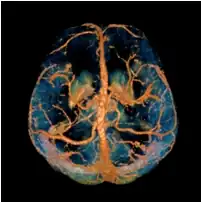

A visualization of the cone in Fourier domain.

In MRI, the local field induced by non-ferromagnetic biomaterial susceptibility along the main polarization B0 field is the convolution of the volume susceptibility distribution with the dipole kernel : . This spatial convolution can be expressed as a point-wise multiplication in Fourier domain:[6][7] . This Fourier expression provides an efficient way to predict the field perturbation when the susceptibility distribution is known. However, the field to source inverse problem involves division by zero at a pair of cone surfaces at the magic angle with respect to B0 in the Fourier domain. Consequently, susceptibility is underdetermined at the spatial frequencies on the cone surface, which often leads to severe streaking artifacts in the reconstructed QSM.